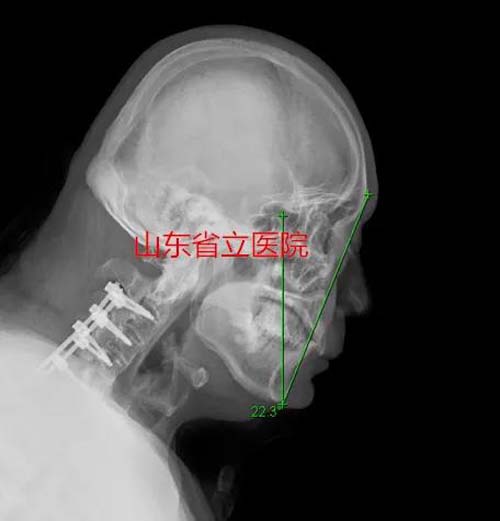

今年54岁的姬先生患强直性脊柱炎多年,他的脊柱渐渐“石化”,尤其是随着病情逐步加重,头部已日益低垂,不能正常抬起,46.1度的颌眉角使他成了一个“颌触胸”的“低头人”,如果想平视或与人交谈,就只能屈膝屈髋,使整个身体呈半蹲状态。行走、平躺睡觉、仰头喝水……这些正常人日常生活中轻而易举做到的动作,姬先生却可望而不可及。半个多月前,一场意外导致的颈椎骨折,使他处于随时可能高位截瘫,甚至危及生命的高度危险状态,慕名到省立医院就诊,开启了他实现“抬头”愿望的第一步。

手术矫形24度,颌眉角由术前的46.1°矫形到术后的22.3°,很好的解决了患者不能抬头的问题,使患者的生活质量得到极大改善。经数月休养后,患者的社会生活和交往必将会极大改善。